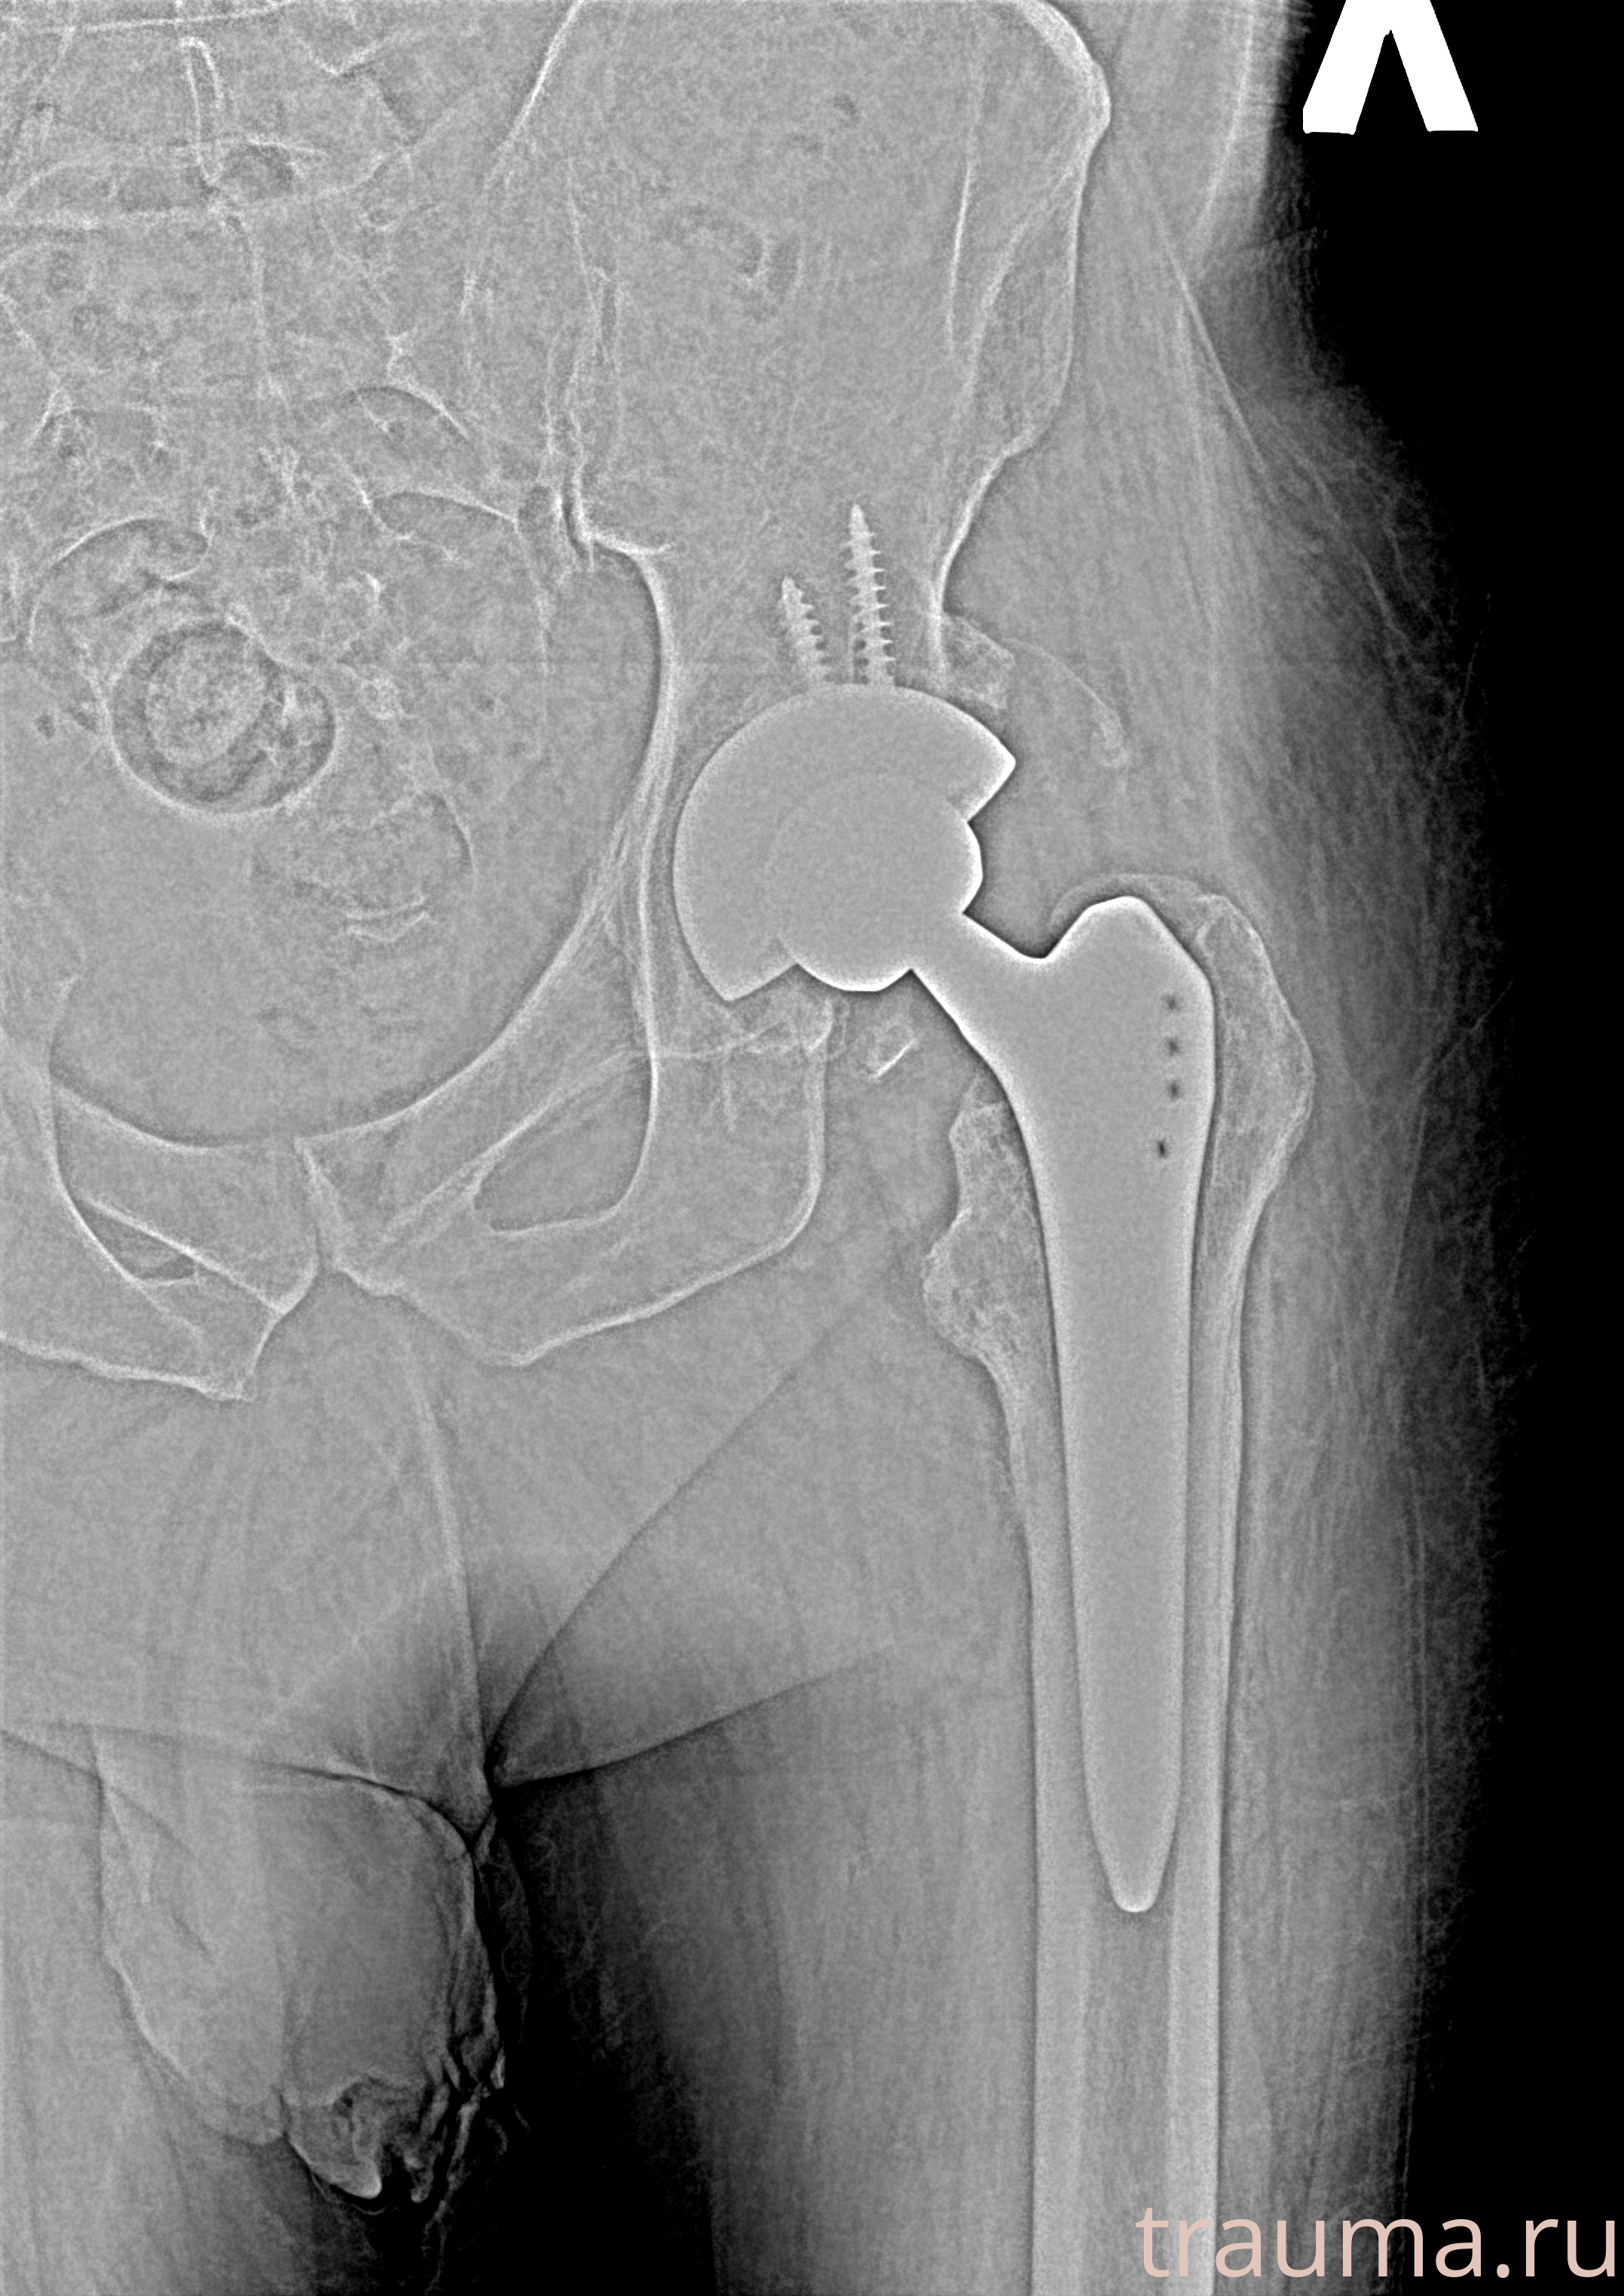

Рентгенограммы